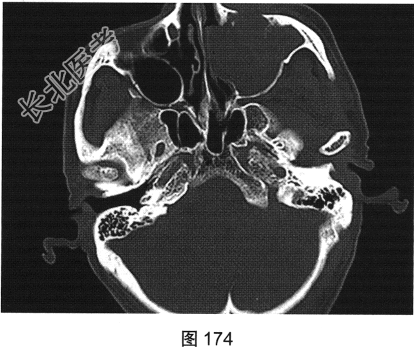

- [材料题] 患者男性,75岁。左侧颌面部肿胀6个月,局部压痛,伴有左侧鼻塞、流涕。CT检查结果如图173~图176所示。

- 简答题1、请问该患者CT表现是什么?

- 简答题2、请问最符合该患者的初步诊断是什么?